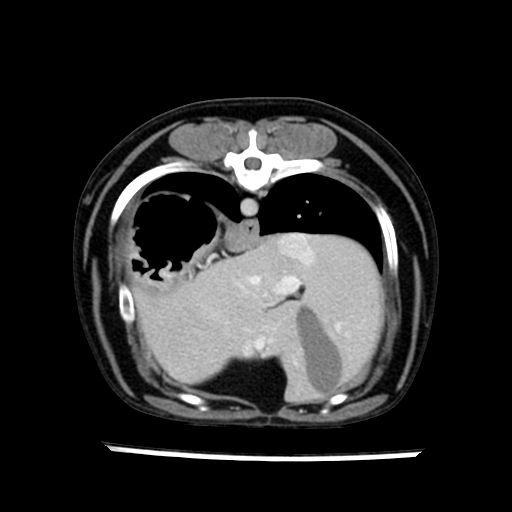

prescritto esame TAC

sequenza immagini limitata al fegato reni e surreni

sospetto adenoma ipofisario vs. meno probabilmente meningioma della base; intertiziopatia polmonare; lesione espansiva epatica, verosimilmente del lobo laterale sinistro, di sospetta natura neoplastica; lesioni spleniche di natura da definire; iperplasia/ipertrofia delle ghiandole surrenali, bilateralmente; vertebra di transizione del rachide toracico; tenosinovite cronica del muscolo bicipite brachiale di destra.

- Nessuna informazione diversa per quello che riguarda l’esame ecografico del fegato e la presa del contrasto si confermano le lesioni individuate e l’ipoenanchement in fase portale.

la tac dopo 7 mesi permette misure tridimensionali 5,2 x 9,2 x 4,5 cm (forma piu’ allungata )